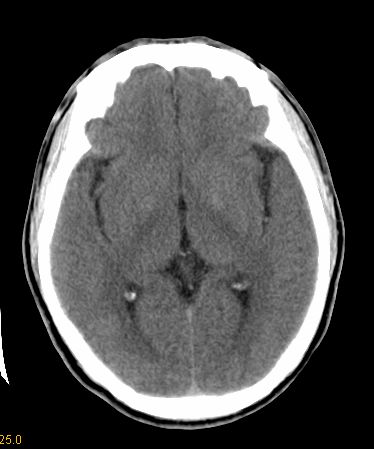

男 42岁 头痛20天

左顶叶占位,不排除转移瘤,建议进一步检查。

左顶叶见片状低密度影,边界不清,内见斑片状等密度影。考虑转移性肿瘤可能性大,建议ct增强或mr增强扫描。建议胸部检查,排除肺部病变。

左顶叶占位,建议进一步检查。

支持左顶叶转移瘤